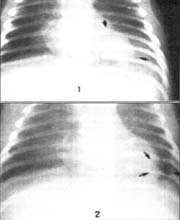

Todos los pacientes en los cuales se sospeche una NN deberían tener una Rx de tórax para definir la localización y presencia de la neumonía, así como la severidad de la misma. De acuerdo a los hallazgos de Mock y cols la presencia de nuevos infiltrados asimétricos o segmentarios persistentes de tipo alveolar, se asociaron con mayor frecuencia a encontrar patógenos en los cultivos de biopsia transbronquial1, 12, 38, 40, 41.

Figura No 2. Neumonía del lóbulo inferior izquierdo por S. aureus. Archivo Radiología FCI.